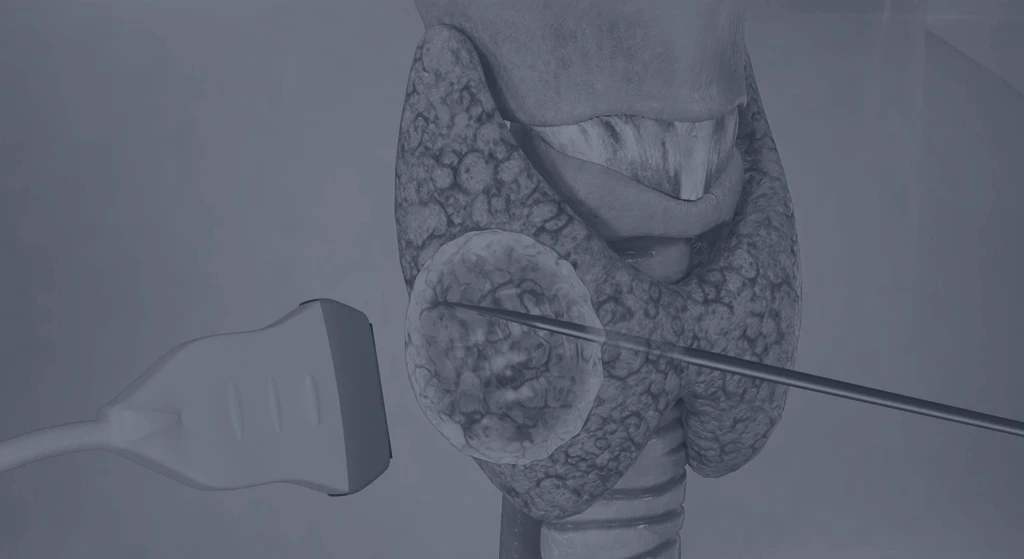

Um espaço seguro, estruturado e preparado para oferecer o melhor em cuidado especializado em Cirurgia de Cabeça e Pescoço.